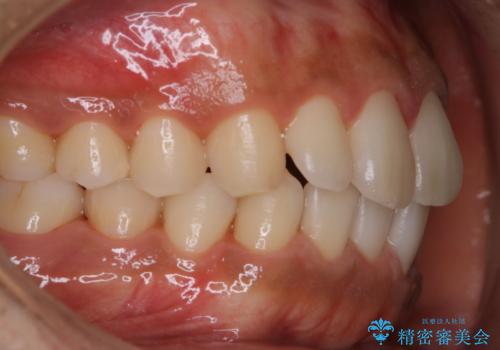

- 特に症状など気になるところはないが、メンテナンスして欲しいとのことでした。染め出しをしてのブラッシング指導とPMTC30分コースを行いました。

磨き残しが多くなると、お口の健康を維持していくのが難しくなってしまいます。お口の健康を守っていくためには、毎日のハミガキを行っていくのが基本です。そのため、なにか症状がなくても定期的に歯科医院で口の健康状態のチェックをすることが大切です。